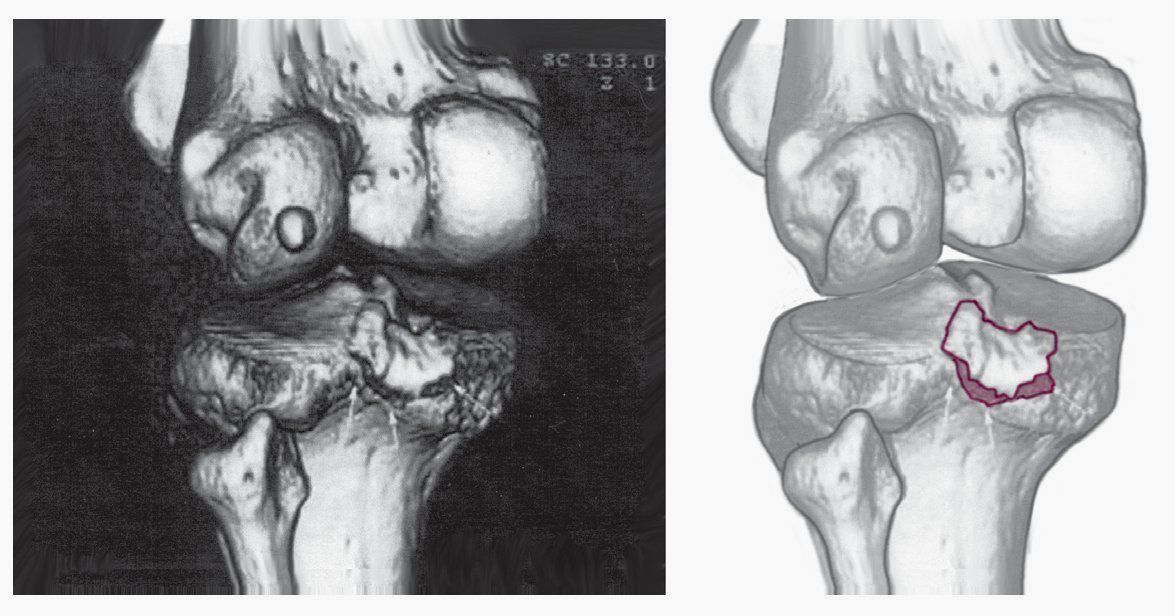

Діагностика пошкоджень задньої хрестоподібної зв'язки

Огляд пацієнтів з підозрою на розрив задньої хрестоподібної зв'язки проводиться у відділенні травматології. Складові діагностики:

- рентген колінного суглоба;

- МРТ колінного суглоба.